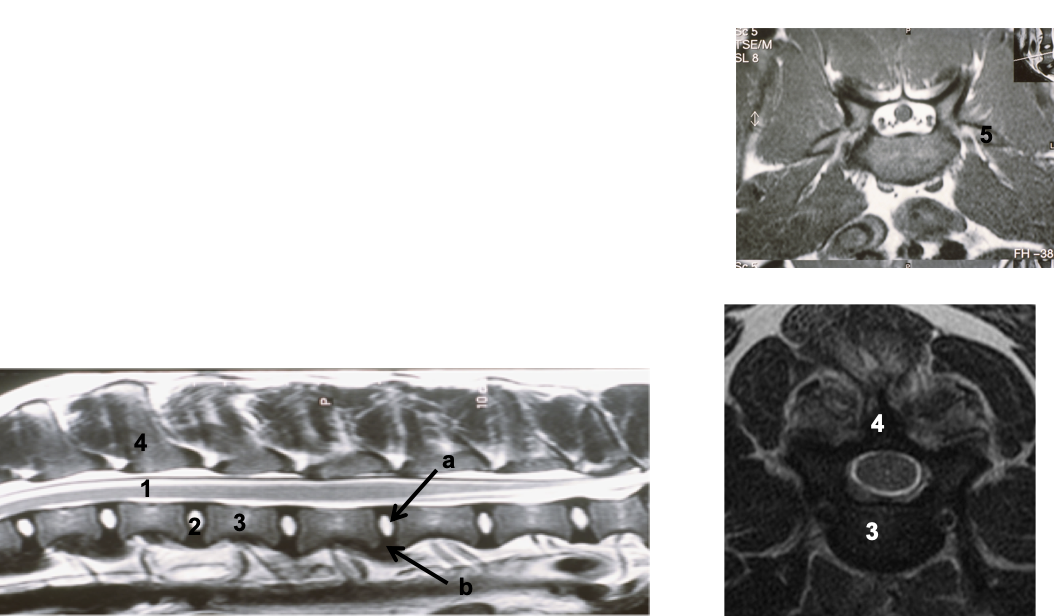

what is a myelogram

injection of contrast medium into vertebral canal (subarachnoid space)

outlines spinal cord

what is the bone window

CT image produced can be altered to enhance the appearance of different tissue types

bone window setting is commonly used for vertebral column

what are the structures shown

why is CT useful

for visualizing boney components –> appear white

no superimposition

brain or soft tissue windows can be used to assess the brain and spinal cord

what are the structures shown and what scan is this

what is seen on T2 weighted imaged

identify the structures